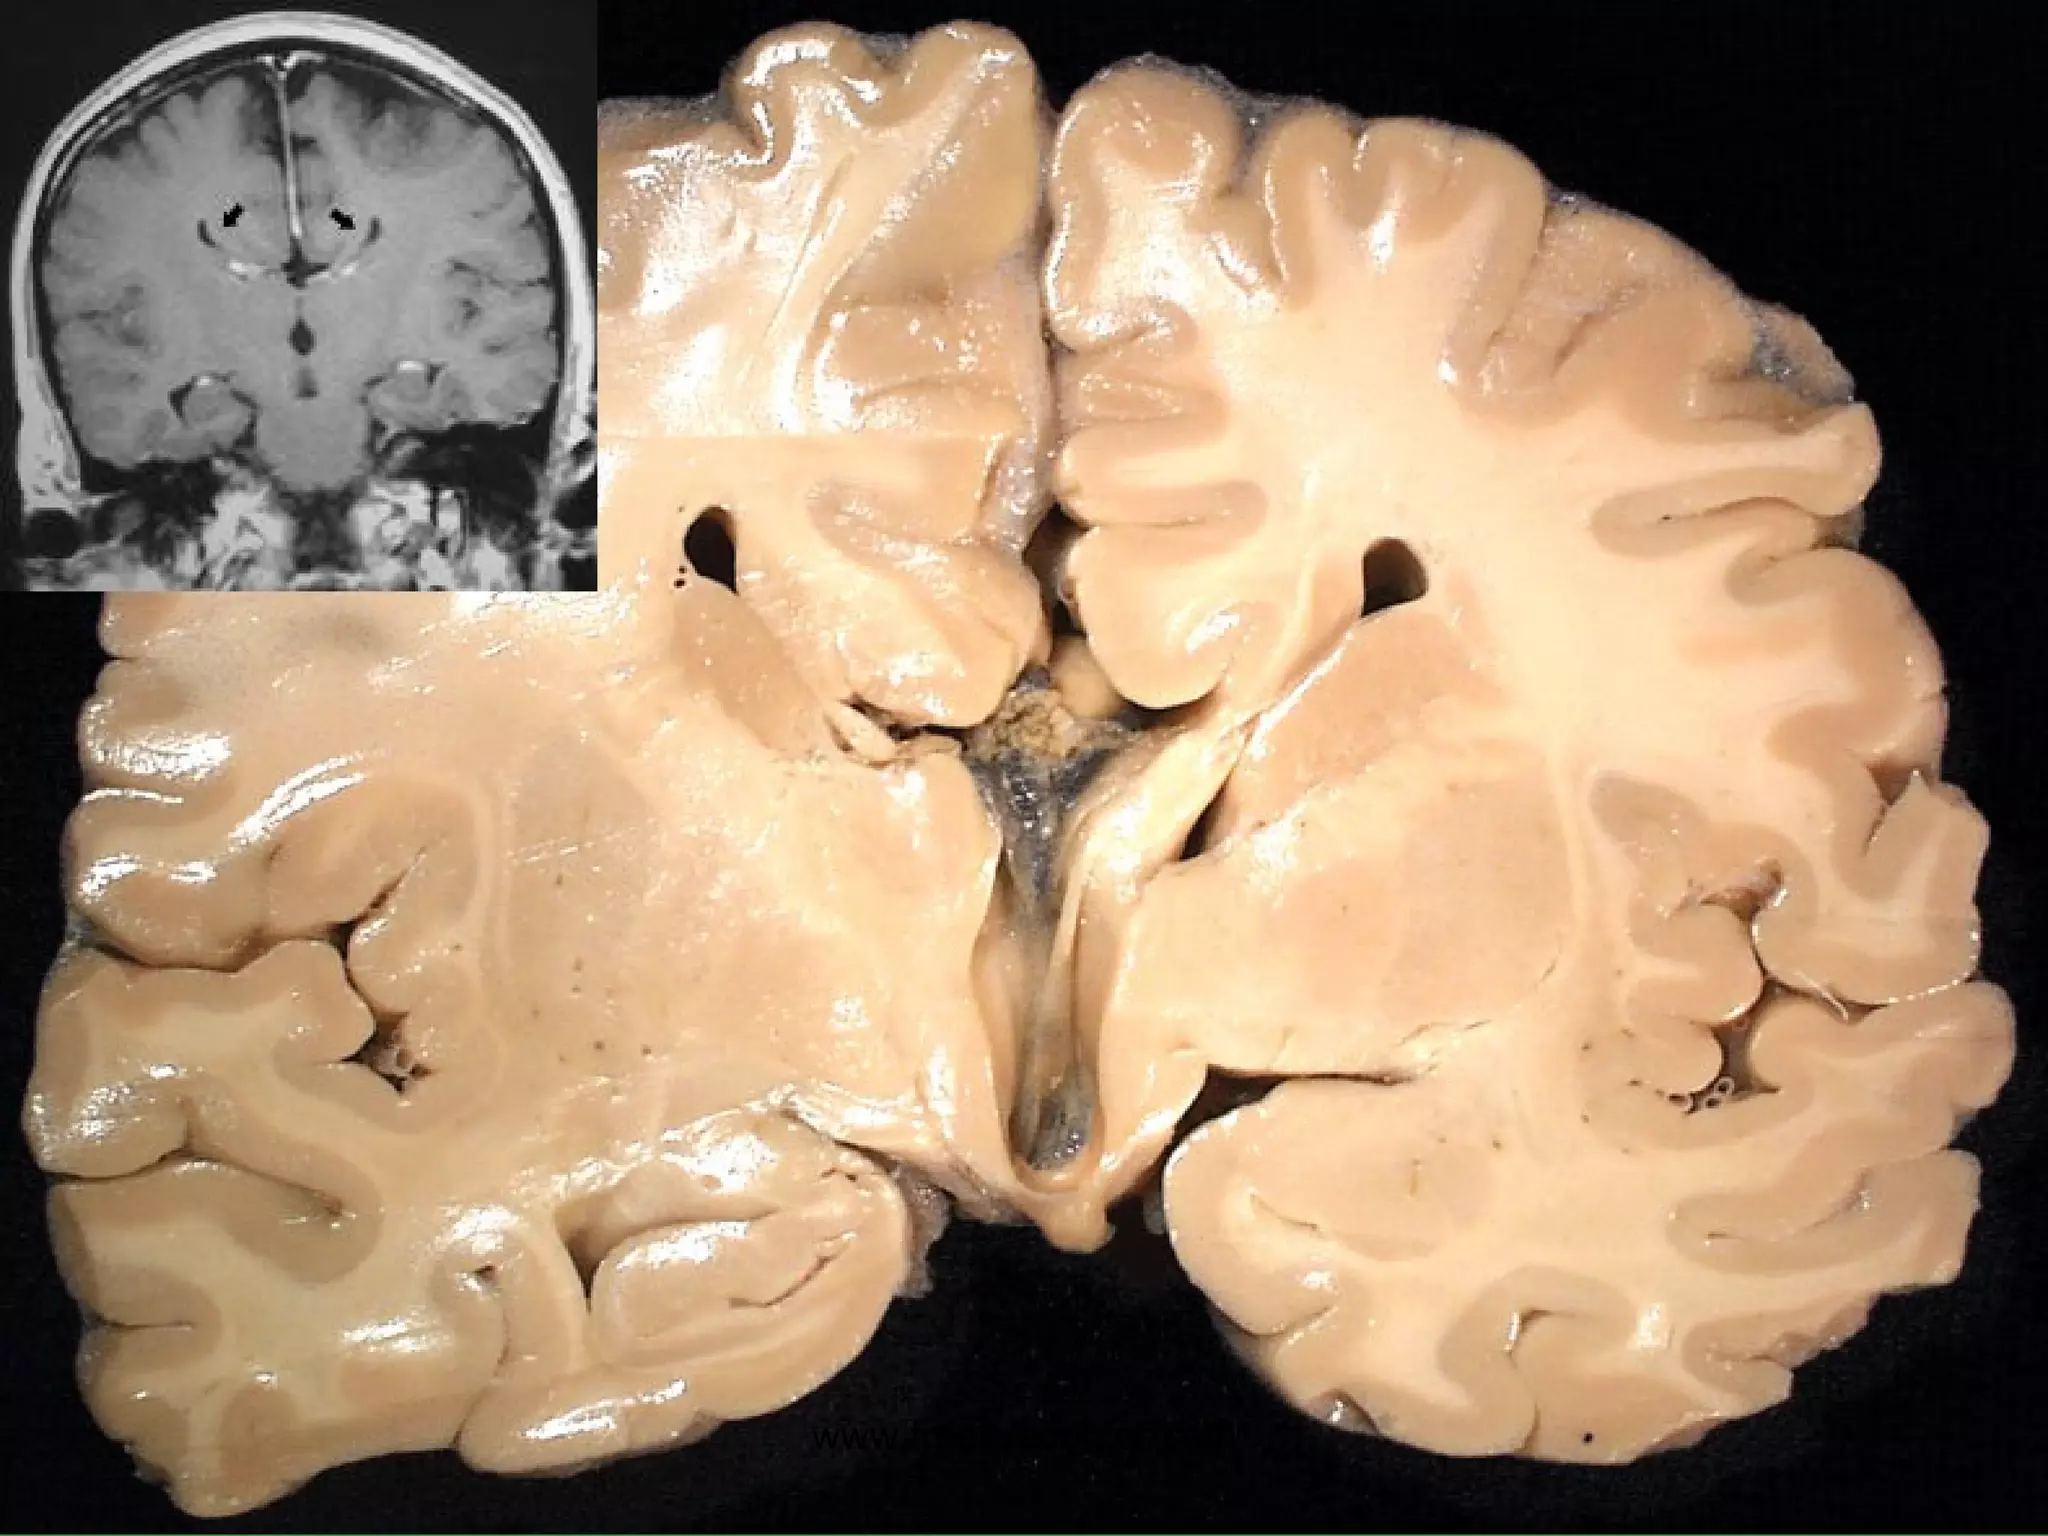

HUNTINGTON DISEASE Classical familial, genetic disease Progressive motor loss and dementia “ chorea”, i.e. “jerky” movements Progressive, fatal Atrophy of basal ganglia, i.e., corpus striatum Cortical (basal ganglia) atrophy Ventricular enlargement www.freelivedoctor.com

• #31 Hydrocephalus also showing cerebral edema, CT or MRI? Ans: CT Why? Ans: Bone is always very dense on CT, and water is always intense on T2 weighted MRI

• #32 Hydrocephalus, dilated ventricles